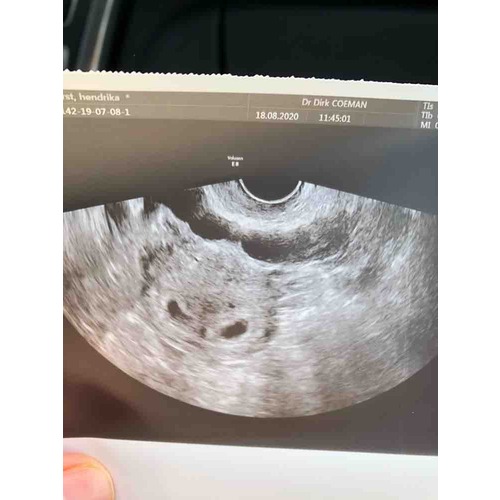

Ja hier 🙋🏼♀️ 5w5 dagen

Nee hoor, dat was mijn zwangerschap, inmiddels zijn de meiden bijna 8 maanden.

Ik vond de zwangerschap lichamelijk heel zwaar, ben op 12 weken al gestopt met werken. Uiteindelijk wel kunnen uitdragen tot 37 weken.